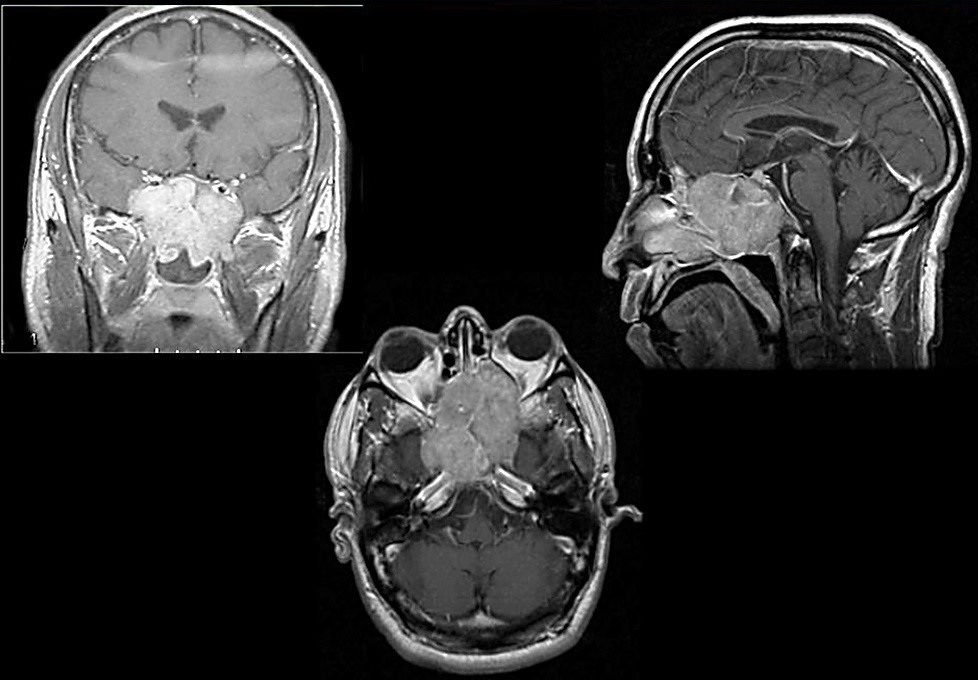

Эстезионейробластома формируется из клеток нейроэпителия. Опухоль располагается в верхней части носового хода, постепенно охватывая пазухи, мозг, основание черепа и орбиту. На снимках выглядит в качестве мягкотканого полипа, который дает метастазы в средостение, шейные лимфатические узлы, кости, легкие, плевру . Этот вид рака носа встречается у пожилых людей, мужчин среднего возраста и детей. Заболевание прогрессирует тремя путями – обостряется ринологическая симптоматика при поражении решетчатого лабиринта, гайморовых пазух, глазницы, обостряется носоглоточная симптоматика при распространении опухоли в носоглотку, хоану или решетчатый лабиринт или обостряется неврологическая симптоматика при прорастании раковых клеток в основание черепа.

- КТ/МРТ пазух носа, верхней челюсти, основания челюсти и глаз. Томография указывает точную локализацию очага опухоли, его распространения на окружающие ткани. Если на снимках есть области затемнения, назначается более детальное обследование;